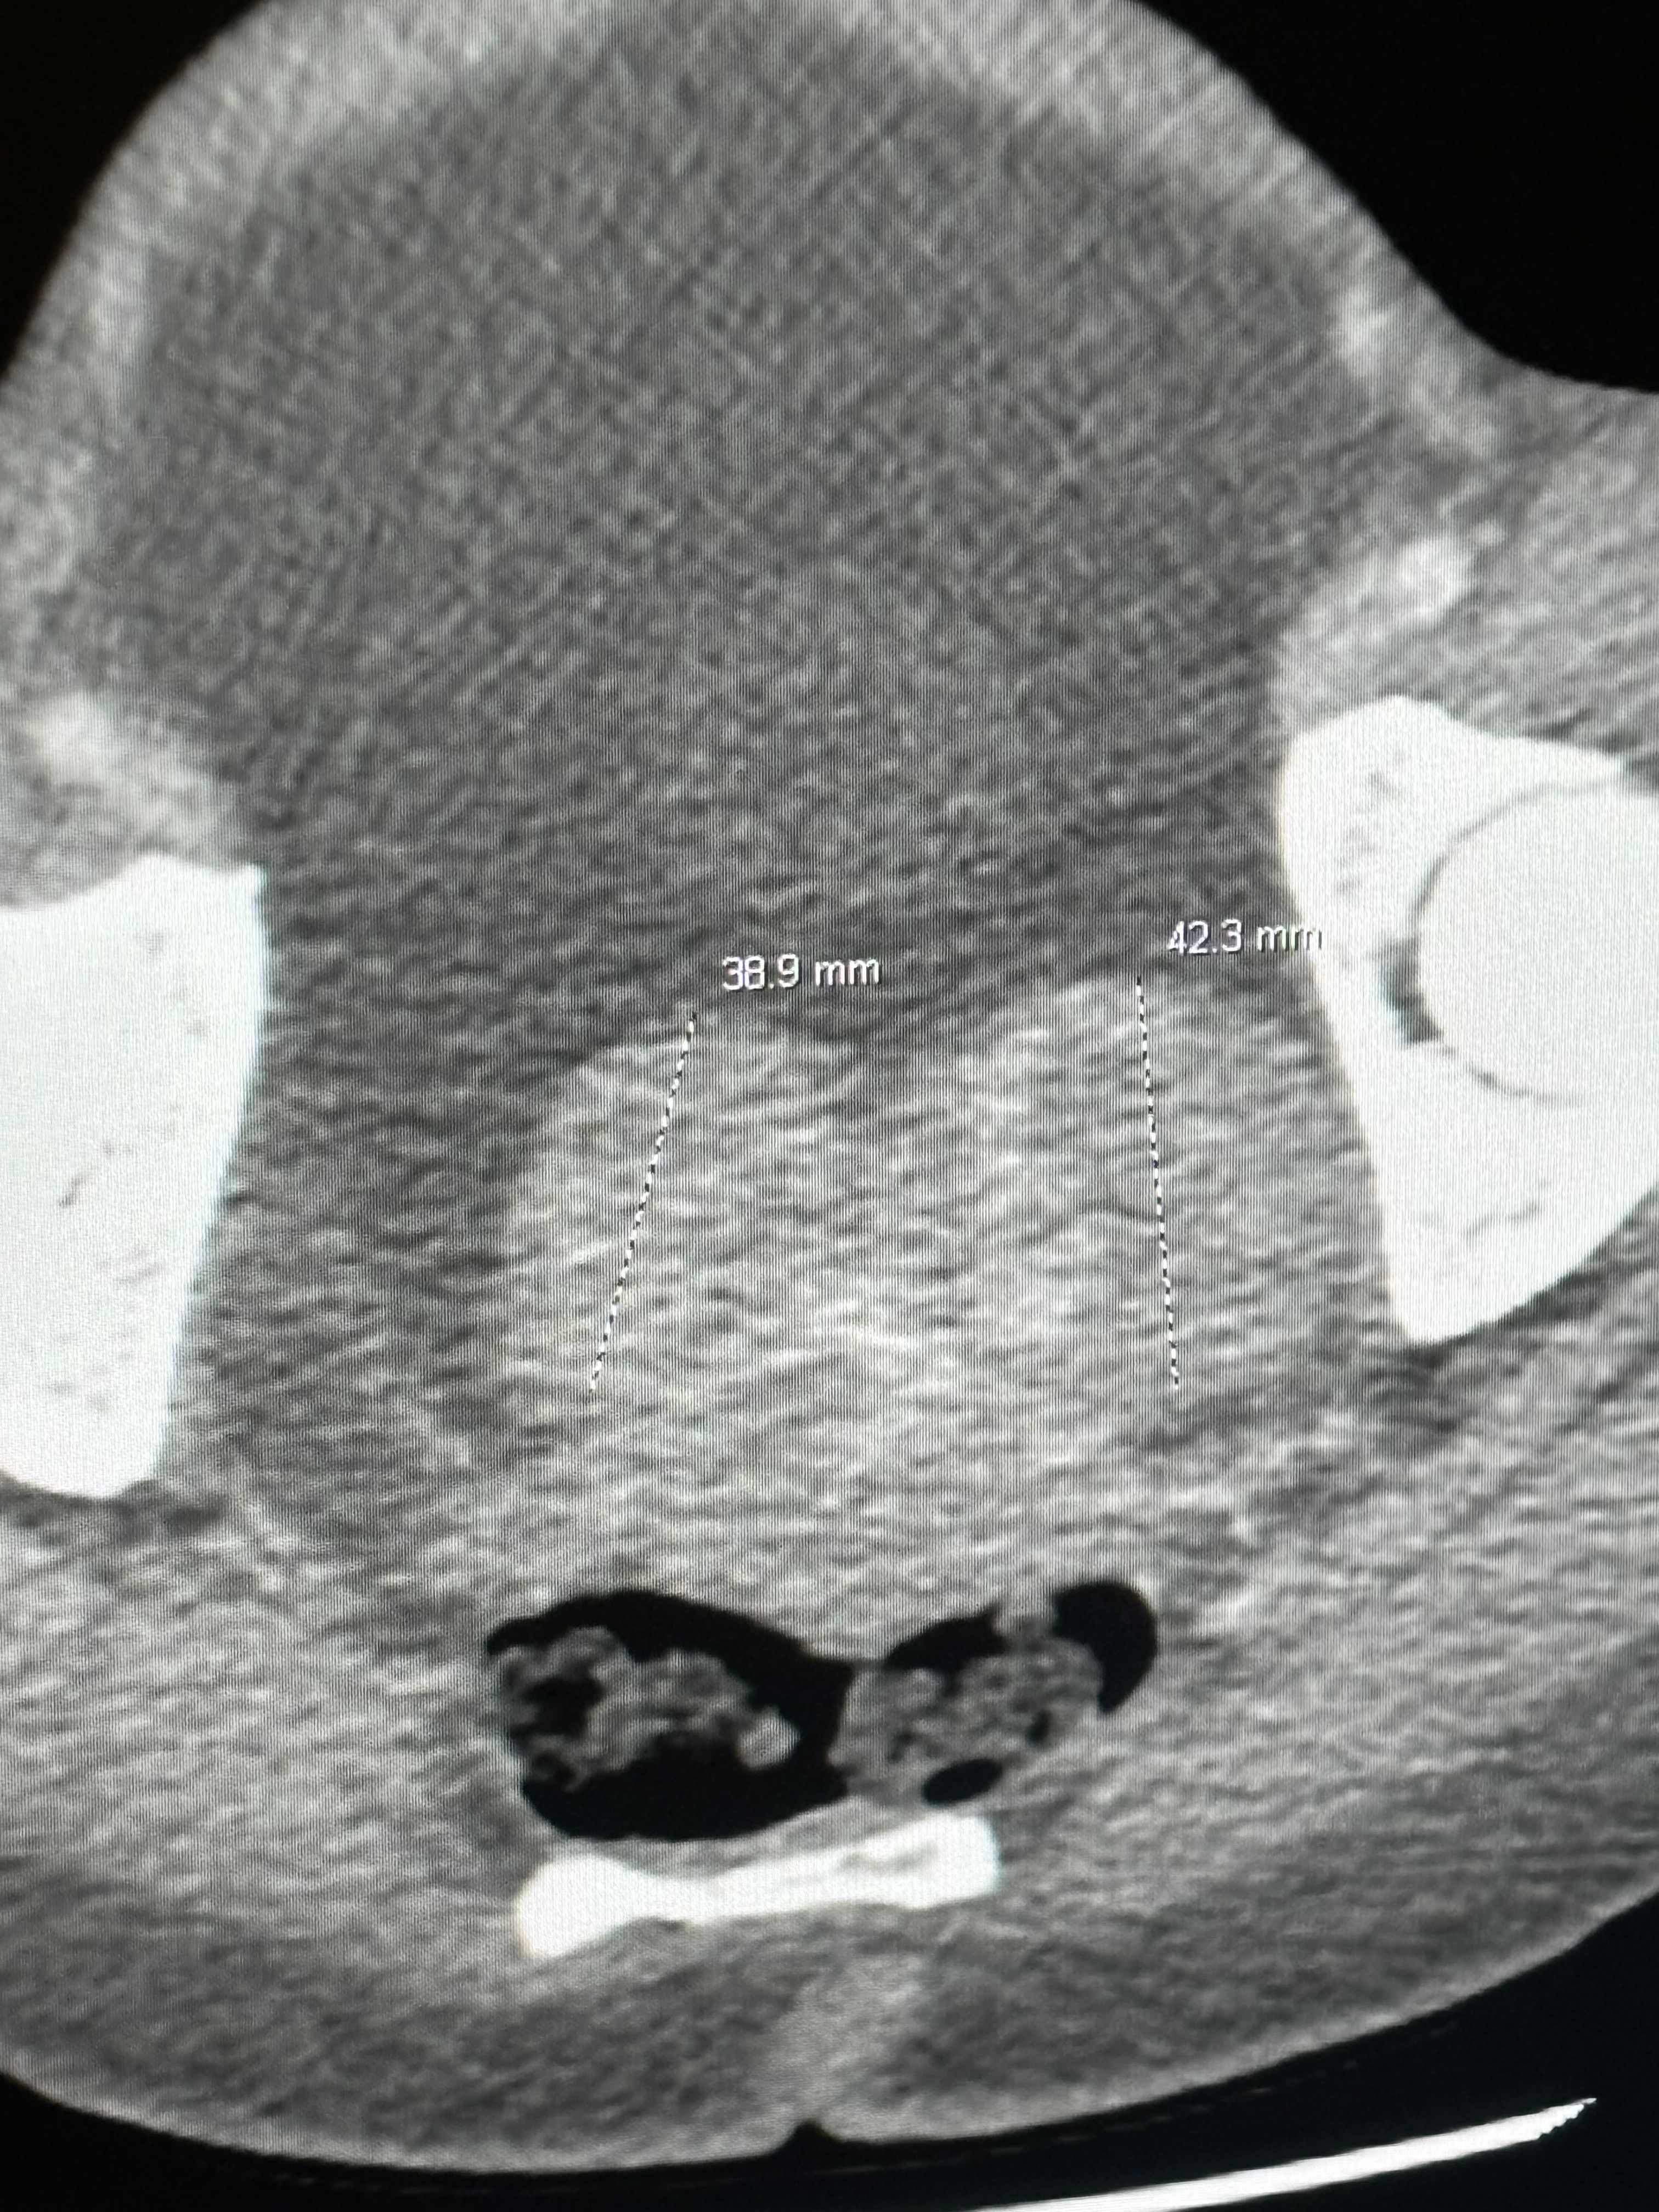

My name is Shanika Littlejohn but I go by diamond Littlejohn is what everybody calls me. In 2024 I was diagnosed with meg syndrome a rare disease and I almost died because of the amount of fluids I had in my stomach, chest and lungs. My fluids purse my heart to the other side of my chest. The first doctor thought it was cancer but thank God no cancer. I do have a fibroid 6.6 inches in diameter and I need surgery to remove it. I am not working at this time because most of the time I be in so much pain. I need help with money to pay bills and medical bills too. I’m supposed to be having surgery next month sometime to remove fibroid from my stomach but they did find a ball of little fibroids in my pelvis that I have to get removed. Thank God my ovaries are fine. I’m not able to eat anything processed and healthy food is very expensive please help me so I can buy the right food and get help with paying my bills. I honestly need help. You can follow me on all my social media accounts under diamond Littlejohn so you can know I’m real. Thank you so much and anything helps, God bless you all and come along on my health journey with me. Book coming soon